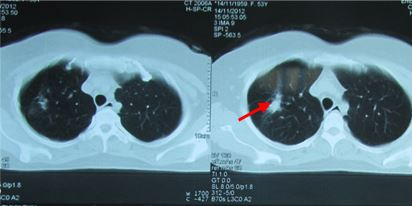

- Chụp CT scanner lồng ngực:

Hình 1: Hình ảnh chụp CT phổi trước điều trị cho thấy u phổi phải kích thước 3,4cm, ngấm thuốc mạnh sau tiêm

Hình 6: U phổi trước điều trị

Hình 7: U phổi sau điều trị 16 tháng, tổn thương xơ hóa nhỏ